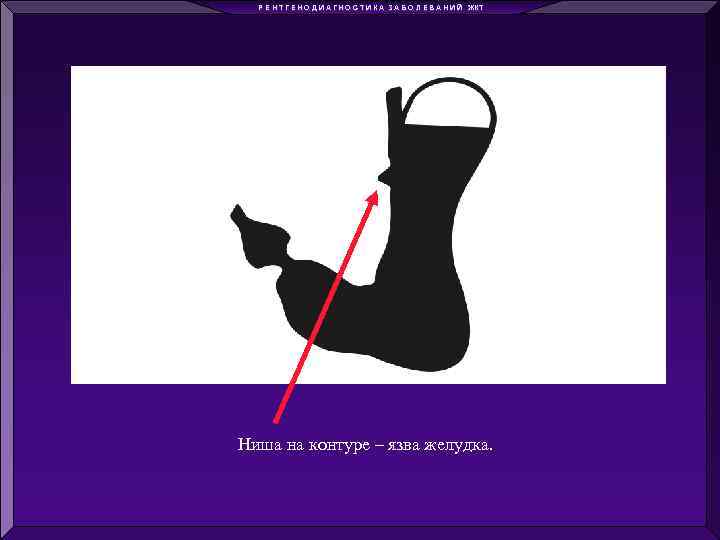

Р Е Н Т Г Е Н О Д И А Г Н О С Т И К А З А Б О Л Е В А Н И Й ЖКТ Ниша на контуре – язва желудка.

Р Е Н Т Г Е Н О Д И А Г Н О С Т И К А З А Б О Л Е В А Н И Й ЖКТ Ниша на контуре – язва желудка.

Р Е Н Т Г Е Н О Д И А Г Н О С Т И К А З А Б О Л Е В А Н И Й ЖКТ Ниша на контуре – язва желудка

Р Е Н Т Г Е Н О Д И А Г Н О С Т И К А З А Б О Л Е В А Н И Й ЖКТ Ниша на контуре – язва желудка